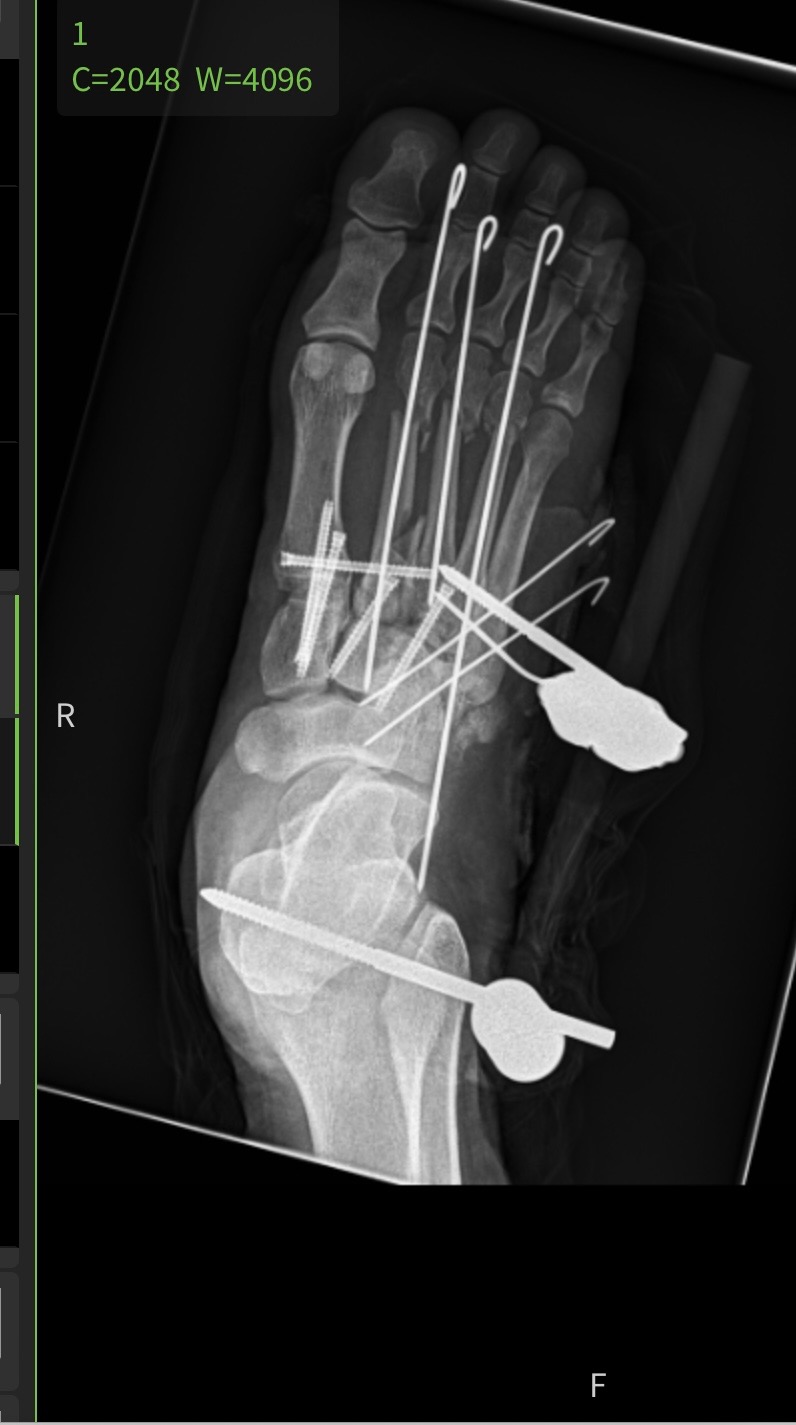

My name is Travis Hillis. In April, I was laid off from my job but was getting unemployment, which was better than nothing while I searched for new work. I found a job working with a friend of mine that I was going to start as soon as possible. Unfortunately, the week I was supposed to go in for paperwork to start work, on Tuesday, July 15th, I had a serious accident while riding a friend's quad in my field looking for a part that was lost from my kid's bike. I made one bad decision to hit the gas while turning to spin the back tires around. The tire caught in dry ground, causing the 700lbs quad to roll. I tried to jump clear of it but got my foot caught while the quad rolled over on top of me, shattering my right foot and breaking my right shoulder. I spent four days and three nights in the hospital before getting released until my second surgery on my foot.

Because of this extremely painful and unfortunate event, I no longer can work or qualify for unemployment, which means I now have zero income and bills stacking up. Just my surgery on Wednesday, 7/23 alone costs just over $70,000.